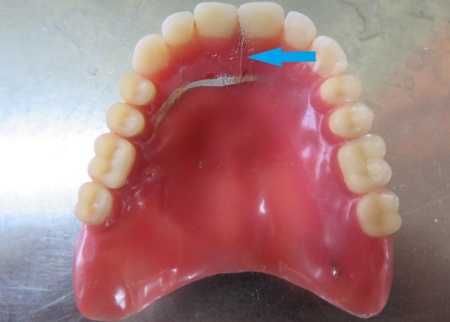

70代女性 ヒビが入った入れ歯に補強線を埋め込む修理をした症例

- 総入れ歯

- 治療期間の目安 -

- 治療回数の目安 1回

-

治療費総額の目安

約2,000円

(保険診療2割負担)

治療のリスク

・着脱式のため、食後の清掃が必要です ・最初のうちは異物感があり、慣れるまで時間がかかる場合があります ・慣れるまでは、入れ歯の裏側の粘膜に傷ができる場合があります...